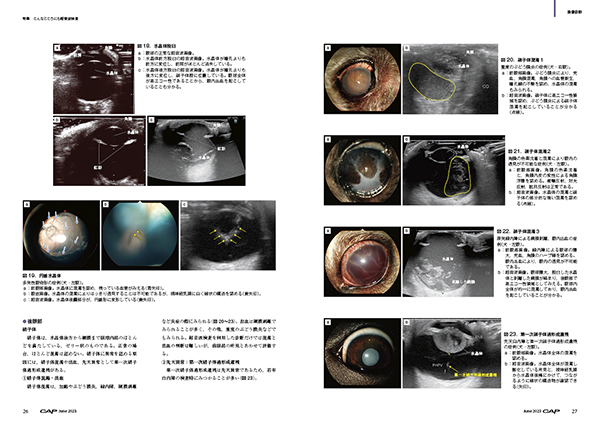

▽眼

都築圭子